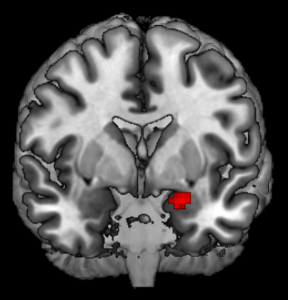

Brain scan made by the researchers showing how the amygdalas of altruistic kidney donors respond more strongly than average. Kristin Brethel-Haurwitz, CC BY-SA

We found some interesting effects while reviewing images captured during this experiment. Most notably, the amygdalas and their periaqueductal gray were more active for kidney donors than people in our control group, with stronger reactions to fearful and distressed stimuli.